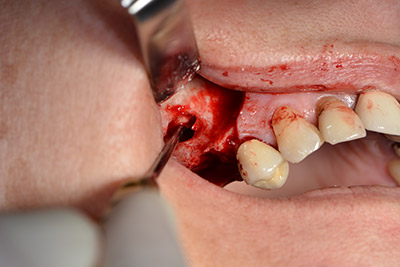

Класическият разрез (крестално, букално освобождаване) и подготовката на мукопериостално ламбо осигуряват добра видимост.

Импланти Sky (Bredent) са използвани в този случай. Хирургичният протокол за тях изисква пилотно пробиване с дрил при 1200  rpm  (Фиг. 9).

Следващата стъпка е синус лифт с непосредствено имплантиране. Implantmed е предварително настроен на първа позиция за букална фенестрация на стената на максиларния синус.

Фенестрацията е извършена при 35,000 rpm и след това носната лигавица е обработена по посока на челюстта (Фиг. 13 to 14).